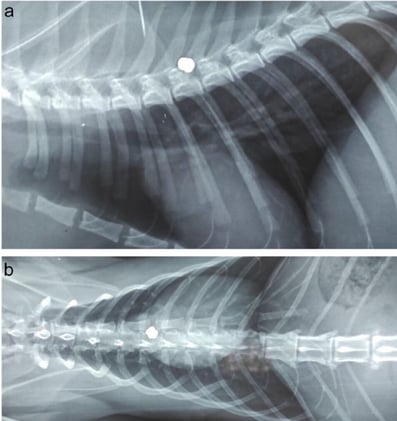

Avian/ExoticsAvian/Exotics

+1+1